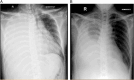

Figure 2

(A, B) Post-contrast thoracic MSCT axial view showed nodules on pleural parietal (red arrow). (C) Post-contrast thoracic MSCT sagittal view showed multiple nodules attached to diaphragm (blue arrow). (D) Right postero-lateral alveolar pleural space (PLAPS) Thoracic ultrasound showed mass attached to diaphragm.